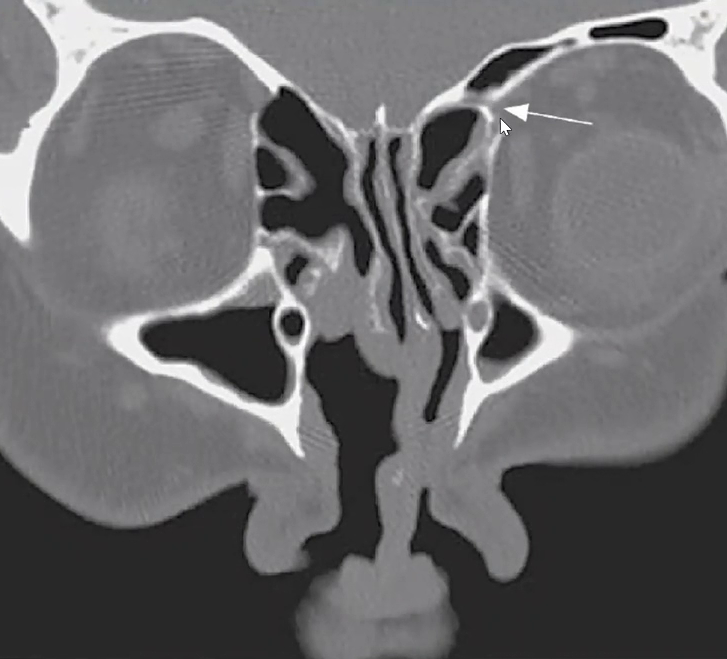

Q

Qual a classificação de Keros nessa imagem?

A

Keros tipo 3 (8-16mm)

Qual o nome da estrutura apontada abaixo e ela é limite de qual região?

ARTÉRIA ETMOIDAL ANTERIOR

• FORMA O LIMITE PÓSTERO-INFERIOR DO RECESSO DO FRONTAL (no teto do etmóide).

• Sai da órbita pelo canal ósseo e vai em direção á lamela lateral da lâmina cribiforme.

Todo cuidado deve ser tomado com a artéria etmoidal anterior medialmente, porque as paredes ósseas ali são muito finas e a dura-máter muito aderida a elas (risco de fístula). E o limite lateral do canal ósseo dela penetra na órbita (risco de lesar lamina papirácea).